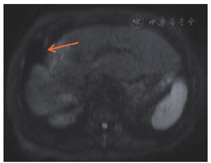

患者77岁男性,因结肠癌术后1年半,发现肝占位2周于2015年12月入院。患者2014年6月行结肠癌根治术(左半结肠),术后经历7个化疗周期(具体方案不详)。2015年12月肝脏增强磁共振示:肝Ⅷ段肿块,大小约32 mm×42 mm×30 mm,考虑转移瘤(图5A);肝门部及后腹膜多发肿大淋巴结(图5B)。肺部CT未见明显异常。肿瘤标志物:癌胚抗原33.8 ng/ml, CA199 493.1 U/ml, CA242 64.4 U/ml, AFP正常。

术后半年内接受12个疗程FOLFIRI化疗方案(伊立替康170 mg/m2,ivgtt+氟尿嘧啶300 mg/m2,ivgtt+氟尿嘧啶1.0 g/m2,civ+亚叶酸钙360 mg/m2,ivgtt),2016年6月复查肝脏增强磁共振提示肺部CT均未见转移或复发征象。2016年9月肝脏增强磁共振提示:术区周围及肝右叶多发环形强化小结节,首先考虑转移,腹膜后多发淋巴结,部分增大(图6)。2016年10月开始接受4个疗程西妥昔单抗+伊立替康单药化疗(伊立替康170 mg/m2+西妥昔单抗800 mg,ivgtt);2016年12月肝Ⅷ段转移灶及腹膜后淋巴结转移灶较前缩小(图7),继续10个疗程西妥昔单抗+伊立替康单药化疗;2017年6月肝转移灶较前明显缩小,继续上述化疗方案。随访至2017年8月19日,患者生存时间超过37个月。